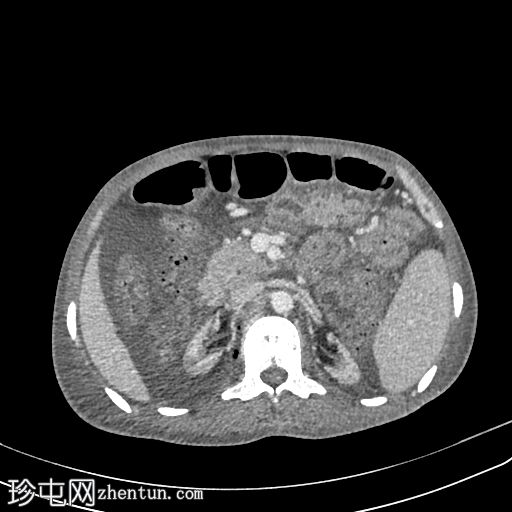

轴位增强扫描(门静脉期)

移植肾位于右髂窝,增大(15 cm),肾实质被异常气体和非强化物质(坏死组织/液体)所取代,提示重度气肿性肾盂肾炎,肾实质破坏超过95%。

仅有少量肾实质强化(不足5%)。

移植肾动脉通畅。

移植肾静脉未见。

右侧腹膜后间隙及右侧腰大肌内可见中等量液体和气体,自肝下区延伸。

中度盆腔腹水。

膀胱萎陷。

弥漫性骨密度增高(?肾性骨营养不良的特征)。